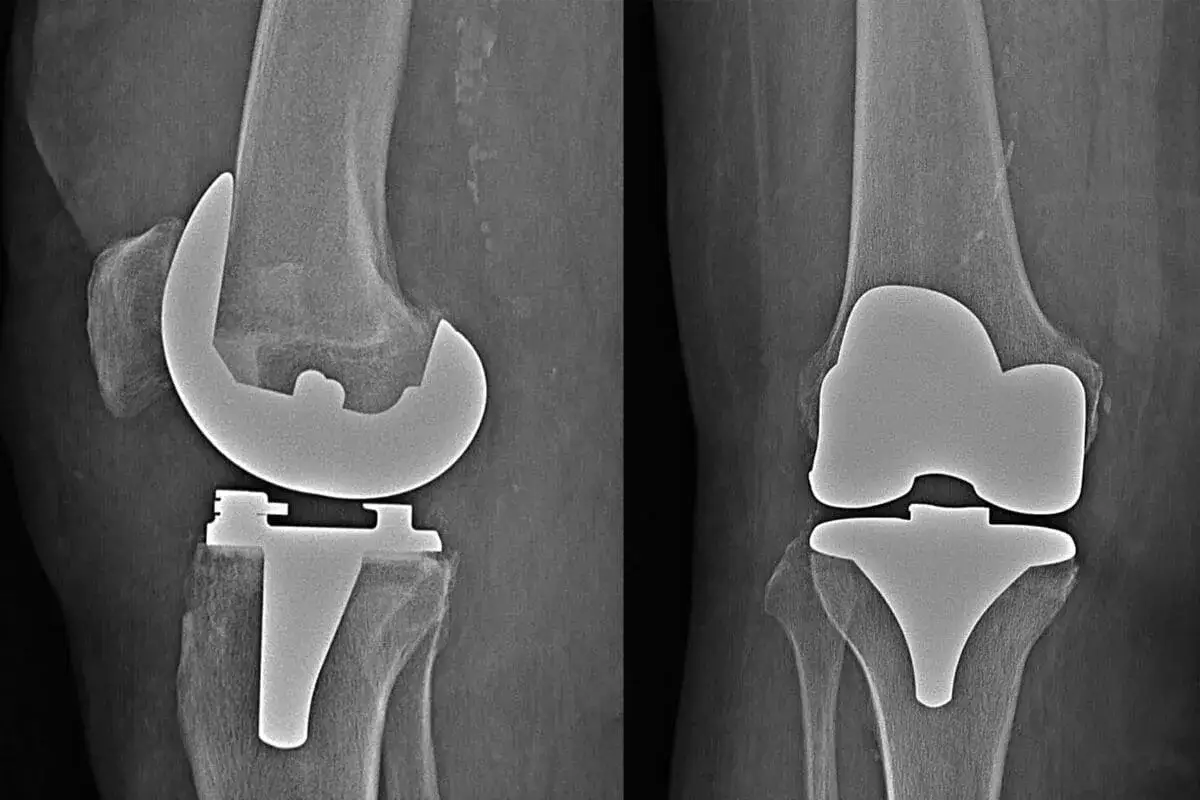

Długie kolejki do specjalistów i zabiegów w ramach Narodowego Funduszu Zdrowia to rzeczywistość, z którą mierzy się wielu pacjentów w Polsce. Jeśli ból kolana staje się nie do zniesienia, a perspektywa wieloletniego oczekiwania na endoprotezę wydaje się paraliżująca, ten artykuł jest dla Ciebie. Pokażemy Ci, jak aktywnie zarządzać swoim miejscem w systemie i znaleźć placówkę z najkrótszym możliwym terminem operacji, wykorzystując oficjalne narzędzia NFZ.

Ból kolana, szczególnie ten wynikający ze zmian zwyrodnieniowych wymagających endoprotezoplastyki, potrafi skutecznie wyłączyć z życia codziennego. Niestety, w Polsce pacjenci często zmagają się nie tylko z dolegliwościami, ale i z perspektywą długiego oczekiwania na zabieg w ramach publicznej służby zdrowia. Zrozumienie, dlaczego te kolejki są tak długie, to pierwszy krok do znalezienia rozwiązania.